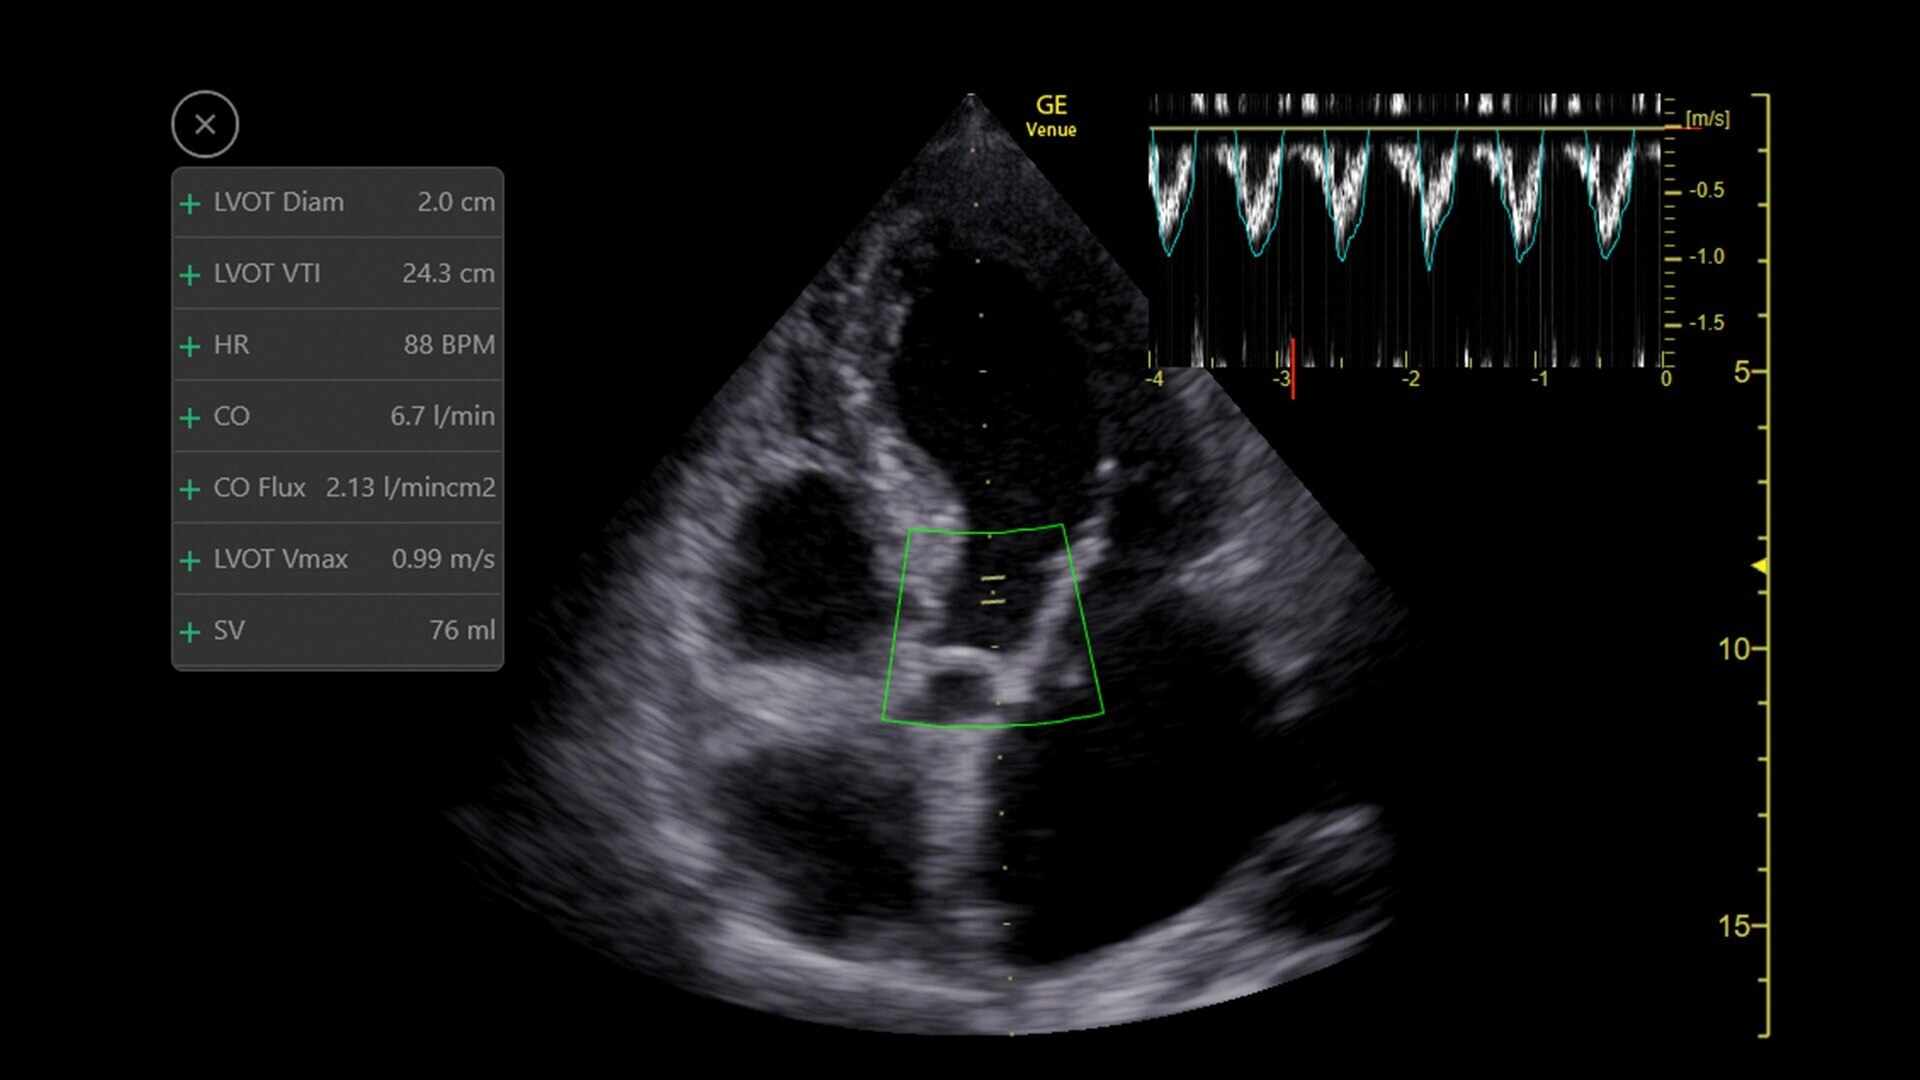

Simplify your workflow with AI-enabled clinical tools.

Helping drive consistency from user to user (whether one is an ultrasound novice or expert), Venue Fit features AI-enabled resources that help clinicians work smarter and more efficiently. Utilizing proprietary algorithms, we synthesize data from numerous patients to ensure accurate calculations for clinical confidence.